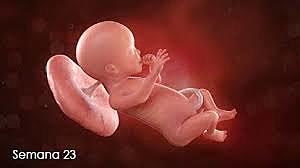

• Semana 23

38

Semana 23

La médula ósea comienza a producir células sanguíneas.

Se desarrollan las vías respiratorias bajas del bebé, pero aún no producen agente

tensioactivo